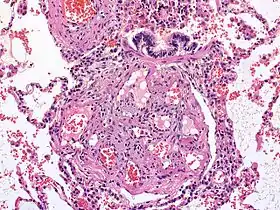

![]() آفه ضفيرية - فرط ضغط الدم الرئوي آفه ضفيرية - فرط ضغط الدم الرئوي | |